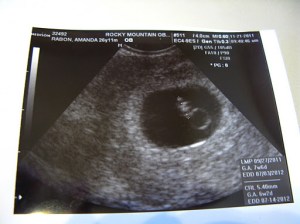

After the longest week of my life, we went back on November 21. They used a much fancier ultrasound machine this time and within seconds we could see Baby’s little heart fluttering on the ultrasound. Right away, I felt all the anxiety go away and felt secure in our pregnancy. The ultrasound tech was even able to find Baby’s heartbeat with the doppler and we could hear it! There’s nothing like that feeling. Baby measured at 6 weeks, 2 days, which was about 11 days younger than we had estimated based on my last period. The heartbeat was at 90 beats per minute. They said that was a little slow and asked us to come back in a week to check to be sure it would speed up.

That week was Thanksgiving and we spent it with my parents. We were all happy and loving the fact that a new little member of our family would be born in a few months. I posted our ultrasound picture on Facebook as we were happy and confident that our little one would be okay.